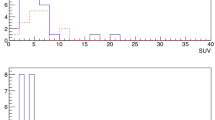

How these two conditions allow to identify possible lesions having different countings topologies is clarified in Fig. 2.

Effect of the two detection conditions (Eqs. 2 and 3). In this example, a 20 s acquisition was performed on a sample, having a cutoff value of 100 CPS (horizontal line), considering the algorithm parameters: \({\upepsilon }_{{\text{Num}}}=4\) and \({\upepsilon }_{{\text{Frac}}}=30\mathrm{\%}\). The color of the legend text suggests whether the two detection conditions were satisfied (red, indicating tumor) or not (green, indicating free of tumor). A red outline of the total legend means that the algorithm identified the sample as Probe + (indicating tumor)

As described in the “Signal-to-background ratio discrimination algorithm” section, the surgically collected dataset was used to statistically calculate the best SBR discrimination algorithm for surgery, i.e., the one having the most optimal sensitivity and specificity as compared to pathology. To this end, the dataset was randomly split in such a way as to have two sub-datasets comprising a similar amount of positive and negative samples. In particular, among all possible combinations, the train dataset contained a total of 35 samples, while the test dataset contained 31 samples. The procedure described in the “Signal-to-background ratio discrimination algorithm” section was then applied to the train dataset: 28 (= \({{N}^{{\text{Values}}}}_{{\upepsilon }_{{\text{Frac}}} }\times {{N}^{{\text{Values}}}}_{{\epsilon }_{{\text{Num}}}}\)). ROC curves, having 18 (= \({{N}^{{\text{Values}}}}_{\sigma }\)) points each, were constructed (see Fig. 4A).

A ROC curves obtained as described in the “Signal-to-background ratio discrimination algorithm” section for the train dataset. The circled point represents the most effective cutoff, corresponding to \({\upepsilon }_{{\text{Num}}}=10\), \({\upepsilon }_{{\text{Frac}}}=5\mathrm{\%}\), and \({N}_{\upsigma }=4.5\). B ROC curve obtained for the test dataset, in the case identified as the most effective cutoff in the train dataset (whose sensitivity and specificity are also shown for reference in the red circle). The yellow-circled point represents the performances of this same cutoff in the test dataset. Numbers nearby points refer to the nsigma of the given point

All ROCs were found to have a high area under the curve (AUC) (median 0.911, IQR 0.905–0.921). The best point in this curve, representing the most effective cutoff on this train dataset, is circled in Fig. 4A and was chosen as the one nearest to the 100 − 100 reference value. This was found to be the point relative to \({\epsilon }_{{\text{Num}}}=10\), \({\epsilon }_{{\text{Frac}}}=5\%\), and \({N}_{\sigma }=4.5\), having sensitivity = 86% and specificity = 90%.

Figure 4B compares this best-performing point in the train dataset (red circle) with the corresponding value in the test dataset (yellow circle), found to have 76–93% sensitivity–specificity. Considering the relatively small amount of data points available for this analysis after the splitting, similar values for sensitivity and specificity were therefore found between the two datasets, thus confirming the robustness of the identified cutoff and more generally of the defined approach.

To demonstrate how the suggested signal-to-background cutoff algorithm could assist surgical decision-making in future in vivo studies, Fig. 5 visualizes a typical acquisition of a district in the current surgical dataset, using the best algorithm parameters. In the plot, blue data represent the background measurement phase, while orange and green data represent probe measurements performed respectively on Path.-Positive and Path.-Negative samples. In this specific district example of patient #2, the cutoff value (red horizontal dashed line) was found to be RCutoff = 153 CPS. All countings exceeding this cutoff are red dashed, but only samples also complying with “condition formula 2” or “condition formula 3”, with \({\epsilon }_{{\text{Num}}}=10\), \({\epsilon }_{{\text{Frac}}}=5\%\), are considered probe-positive and have therefore a red border around their label. In the particular case represented in Fig. 5, therefore, thanks to the discrimination algorithm, the probe would have identified 1 true positive and 2 true negatives.

A Example of data acquired when scanning a given district with the best discrimination algorithm. Blue data represent counts considered to evaluate the background, while orange and green ones represent measurements performed on tumor and healthy tissue respectively, according to pathology examination. The label reports the name and pathology code of the considered sample, while the color of its surrounding border represents whether the sample was identified as probe-positive (red) or probe-negative (green) by the algorithm. B, C Screenshots of the DROP-IN probe performing measurements on samples M and N respectively

To compare the performances of the investigated discrimination algorithm with the typical “fixed SBR cutoff approach,” sensitivity and specificity were also calculated for a fixed 1.5 SBR cutoff ratio (60 and 90%, respectively) and 2 SBR cutoff ratio (45 and 97%, respectively; see Fig. 6).